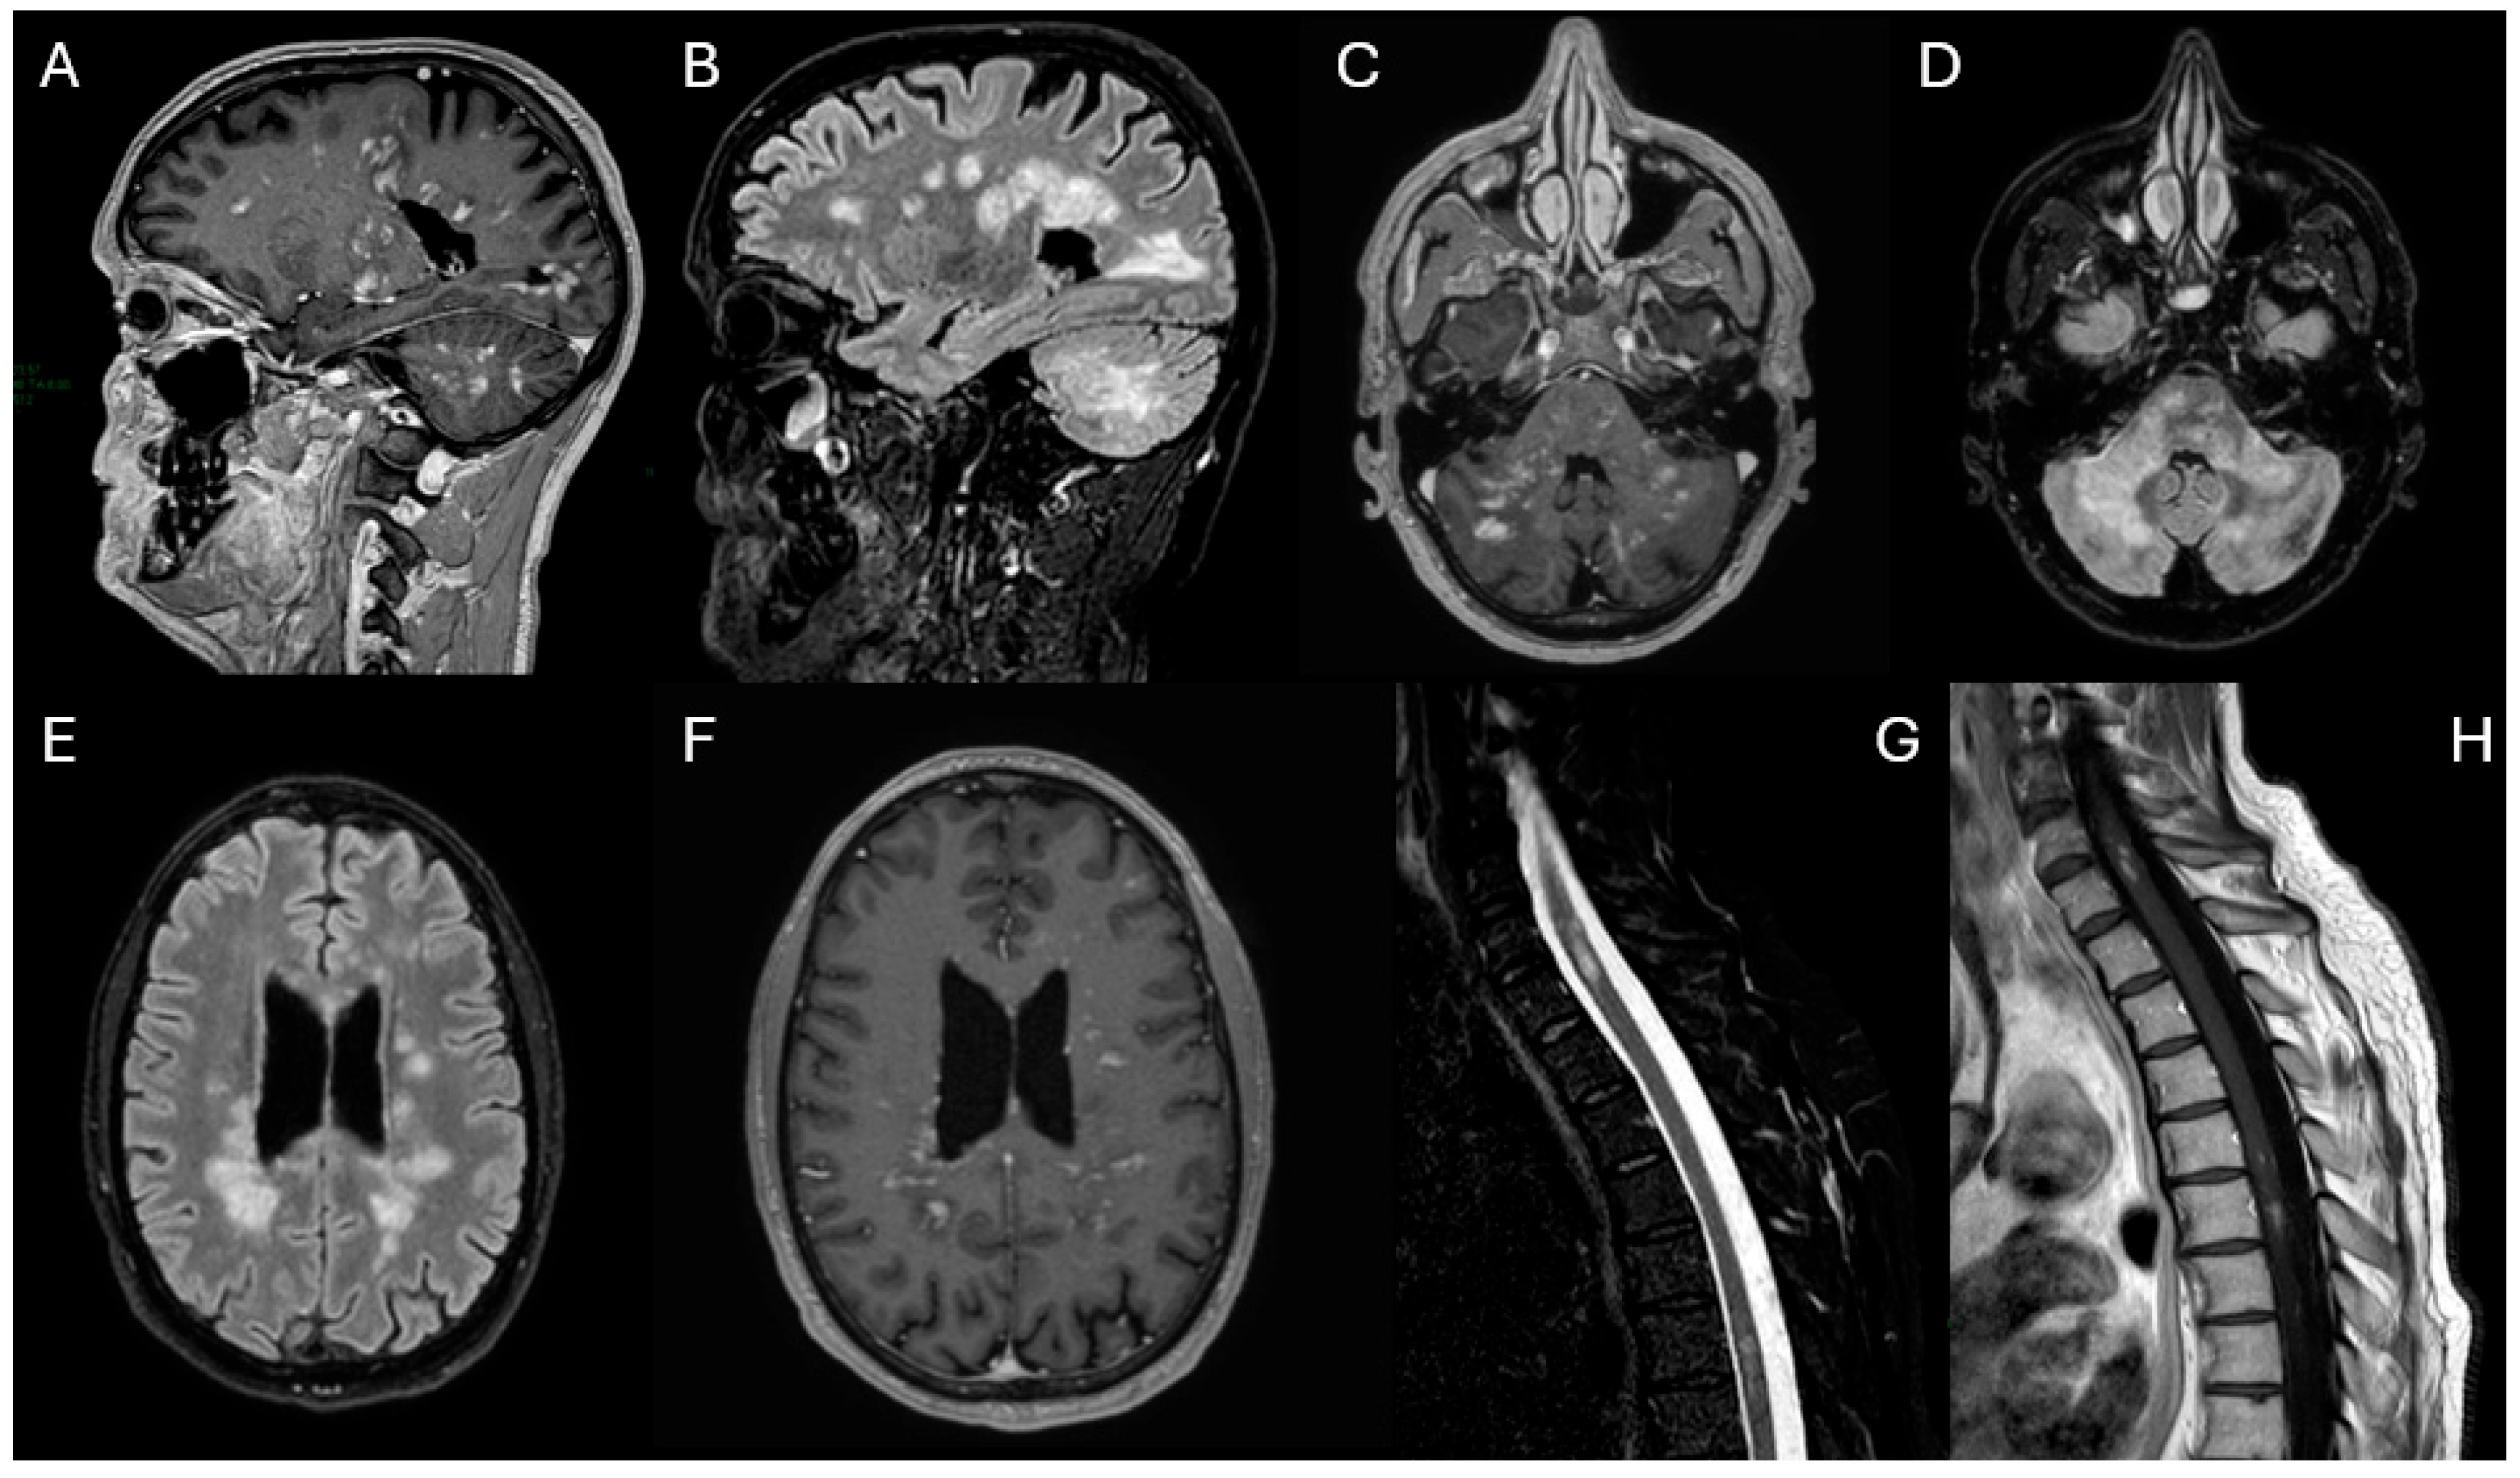

Upon admission to the Neurology Department, a new MRI showed a “mass-like” lesion in the left paratrigonal region with hemorrhagic components, another at the C6 spinal level, and multiple contrast-enhancing lesions were identified in the cerebellum, supratentorial white matter, and spinal cord (Figure 2).

Figure 2. Contrast-enhanced T1-weighted (A,D,GI), fluid-attenuated inversion recovery (FLAIR) (C,E), T2 (F) and SWI (B) images 10 months after. After clinical worsening following corticosteroid therapy, the images reveal the appearance of a lesion with “mass-like” features in the left paratrigonal region (AE), with associated hemorrhagic components (B). Another similar lesion is present at the C6 level in the spinal cord (F,G). Several punctate contrast-enhancing lesions are still present in the cerebellum (H), in the supratentorial white matter (I) and in the spinal cord (G).